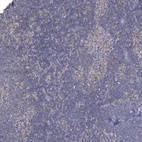

Immunohistochemistry analysis in human testis and skeletal muscle tissues using HPA040446 antibody. Corresponding SPAG9 RNA-seq data are presented for the same tissues.